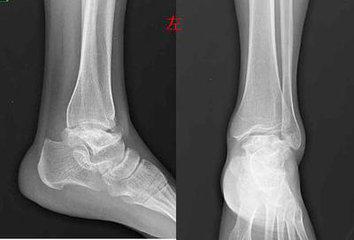

(图:治疗后的左足踝关节X光)

过第三个疗程治疗,孙先生的全身多关节痛风石全部溶解,没有僵硬感,左足踝关节溃烂处基本恢复正常,各个关节活动无阻。

三个月后,孙先生来院复查,全身关节痛风症状全部消失,没有任何不适感,检查报告显示尿酸值恢复到正常值,无需再治疗。陈建春主任特别嘱咐他,今后一定要合理的饮食,多食水果蔬菜,积极锻炼身体,防止疾病再次侵害。